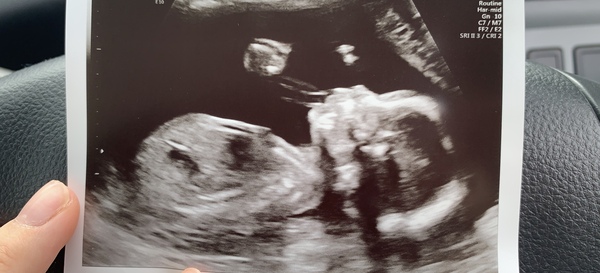

Babyhope98 · 10/07/2020 15:57

Here is my little girl was so proud seeing her there and all was well. Feeling so much movement now, has anyone felt something down below, it almost feels as if some air is released think it must be her moving or something 😅